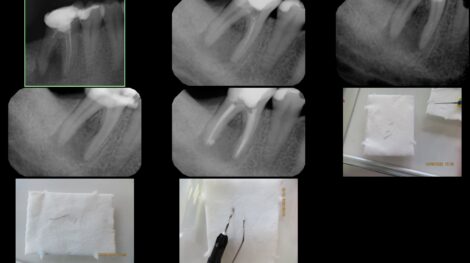

Usunięcie 5 złamanych narzędzi z jednego zęba